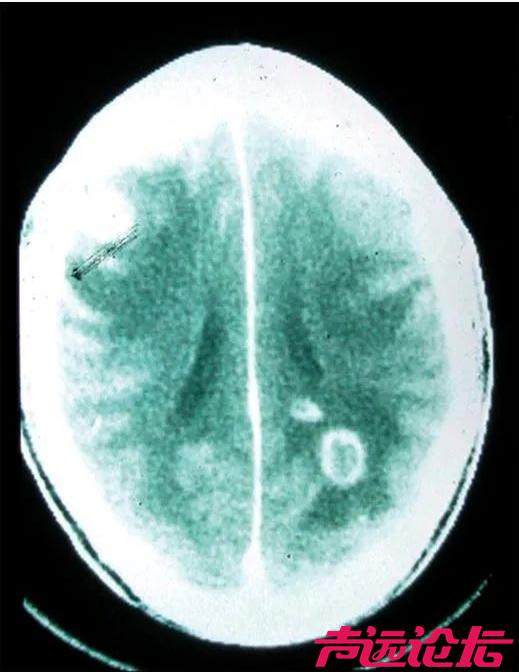

弓形虫感染人类大脑 图片来源:Sullivan & Jeffers, 2012

人体内原本存在一些屏障,将人体重要部位与身体其他部分的内环境分割开来,防止病原体的入侵,但弓形虫却能够跨越这些屏障。例如,它们就能跨越血胎屏障,这就是为何如果孕妇感染了弓形虫,可能对胎儿造成严重的影响,严重时甚至可能导致流产;它们也能跨越血脑屏障,并引起各种中枢神经病症,比如癫痫等。当然,它们也能跨越血睾屏障,对男性的生殖系统产生影响。